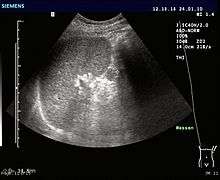

An accessory spleen (supernumerary spleen, splenule, or splenunculus) is a small nodule of splenic tissue found apart from the main body of the spleen. Accessory spleens are found in approximately 10 percent of the population[1] and are typically around 1 centimeter in diameter. They may resemble a lymph node or a small spleen. They form either by the result of developmental anomalies or trauma.[2] They are medically significant in that they may result in interpretation errors in diagnostic imaging[2] or continued symptoms after therapeutic splenectomy.[1]

If splenectomy is performed for conditions in which blood cells are sequestered in the spleen, failure to remove accessory spleens may result in the failure of the condition to resolve.[1] During medical imaging, accessory spleens may be confused for enlarged lymph nodes or neoplastic growth in the tail of the pancreas,[3] gastrointestinal tract, adrenal glands or gonads.[2]